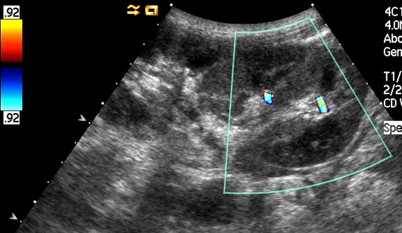

Ultraschall der Nieren

Der Ultraschall der Nieren ist eine der wichtigsten bildgebenden Untersuchungen, um die Gesundheit und Funktion der Nieren zu beurteilen. Bei diesem Verfahren werden Schallwellen verwendet, um ein Bild der Nieren zu erzeugen. Durch den Ultraschall können verschiedene Aspekte der Nieren, wie ihre Größe, Form und Struktur, beurteilt werden. Diese Informationen können Hinweise auf mögliche Erkrankungen oder Probleme geben, wie z.B. Nierensteine, Tumore oder Flüssigkeitsansammlungen. Der Ultraschall der Nieren ist eine sichere und nicht-invasive Untersuchung, die in der Regel keine Schmerzen verursacht und keine Strahlenbelastung beinhaltet. Daher wird sie häufig als erste Untersuchungsmethode für die Bewertung der Nieren eingesetzt.